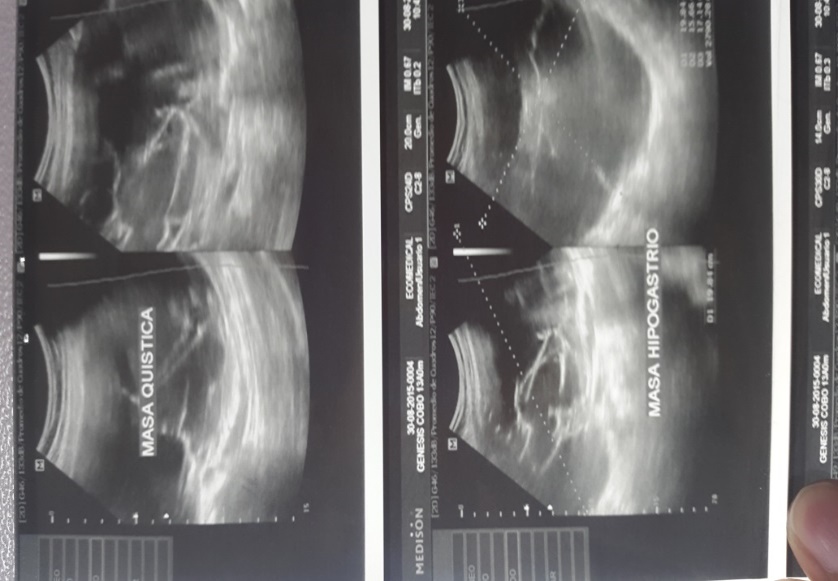

Adolescente de 13 años sin menarquia con dolor abdominal de 4 meses evolución, constipación y aumento del diámetro abdominal, un mes antes del ingreso nota la presencia de una masa dura en región de hipogastrio que se extiende desde la pelvis hasta la región umbilical. La ecografía abdominal evidenció una masa que ocupa todo hipogastrio (figura N°1), la tomografía abdominal mostró una masa dependiente de ovario 15cm de diámetro (figura N°2). Se realizaron los siguientes marcadores tumorales, CA 125, CA 199, ALFAFETROPROTENINA, BHCG, LDH cuyos resultados fueron normales.

Masa quística tabicada de contenido hetrogeneo de 20*15*17cm. Volumen aproximado 280cm

Masa de características quísticas, tabicada, dependiente de anexo derecho

Masa multilobulada de apariencia quística dependiente de anexo derecho de 20 x 15 x 18 cm.